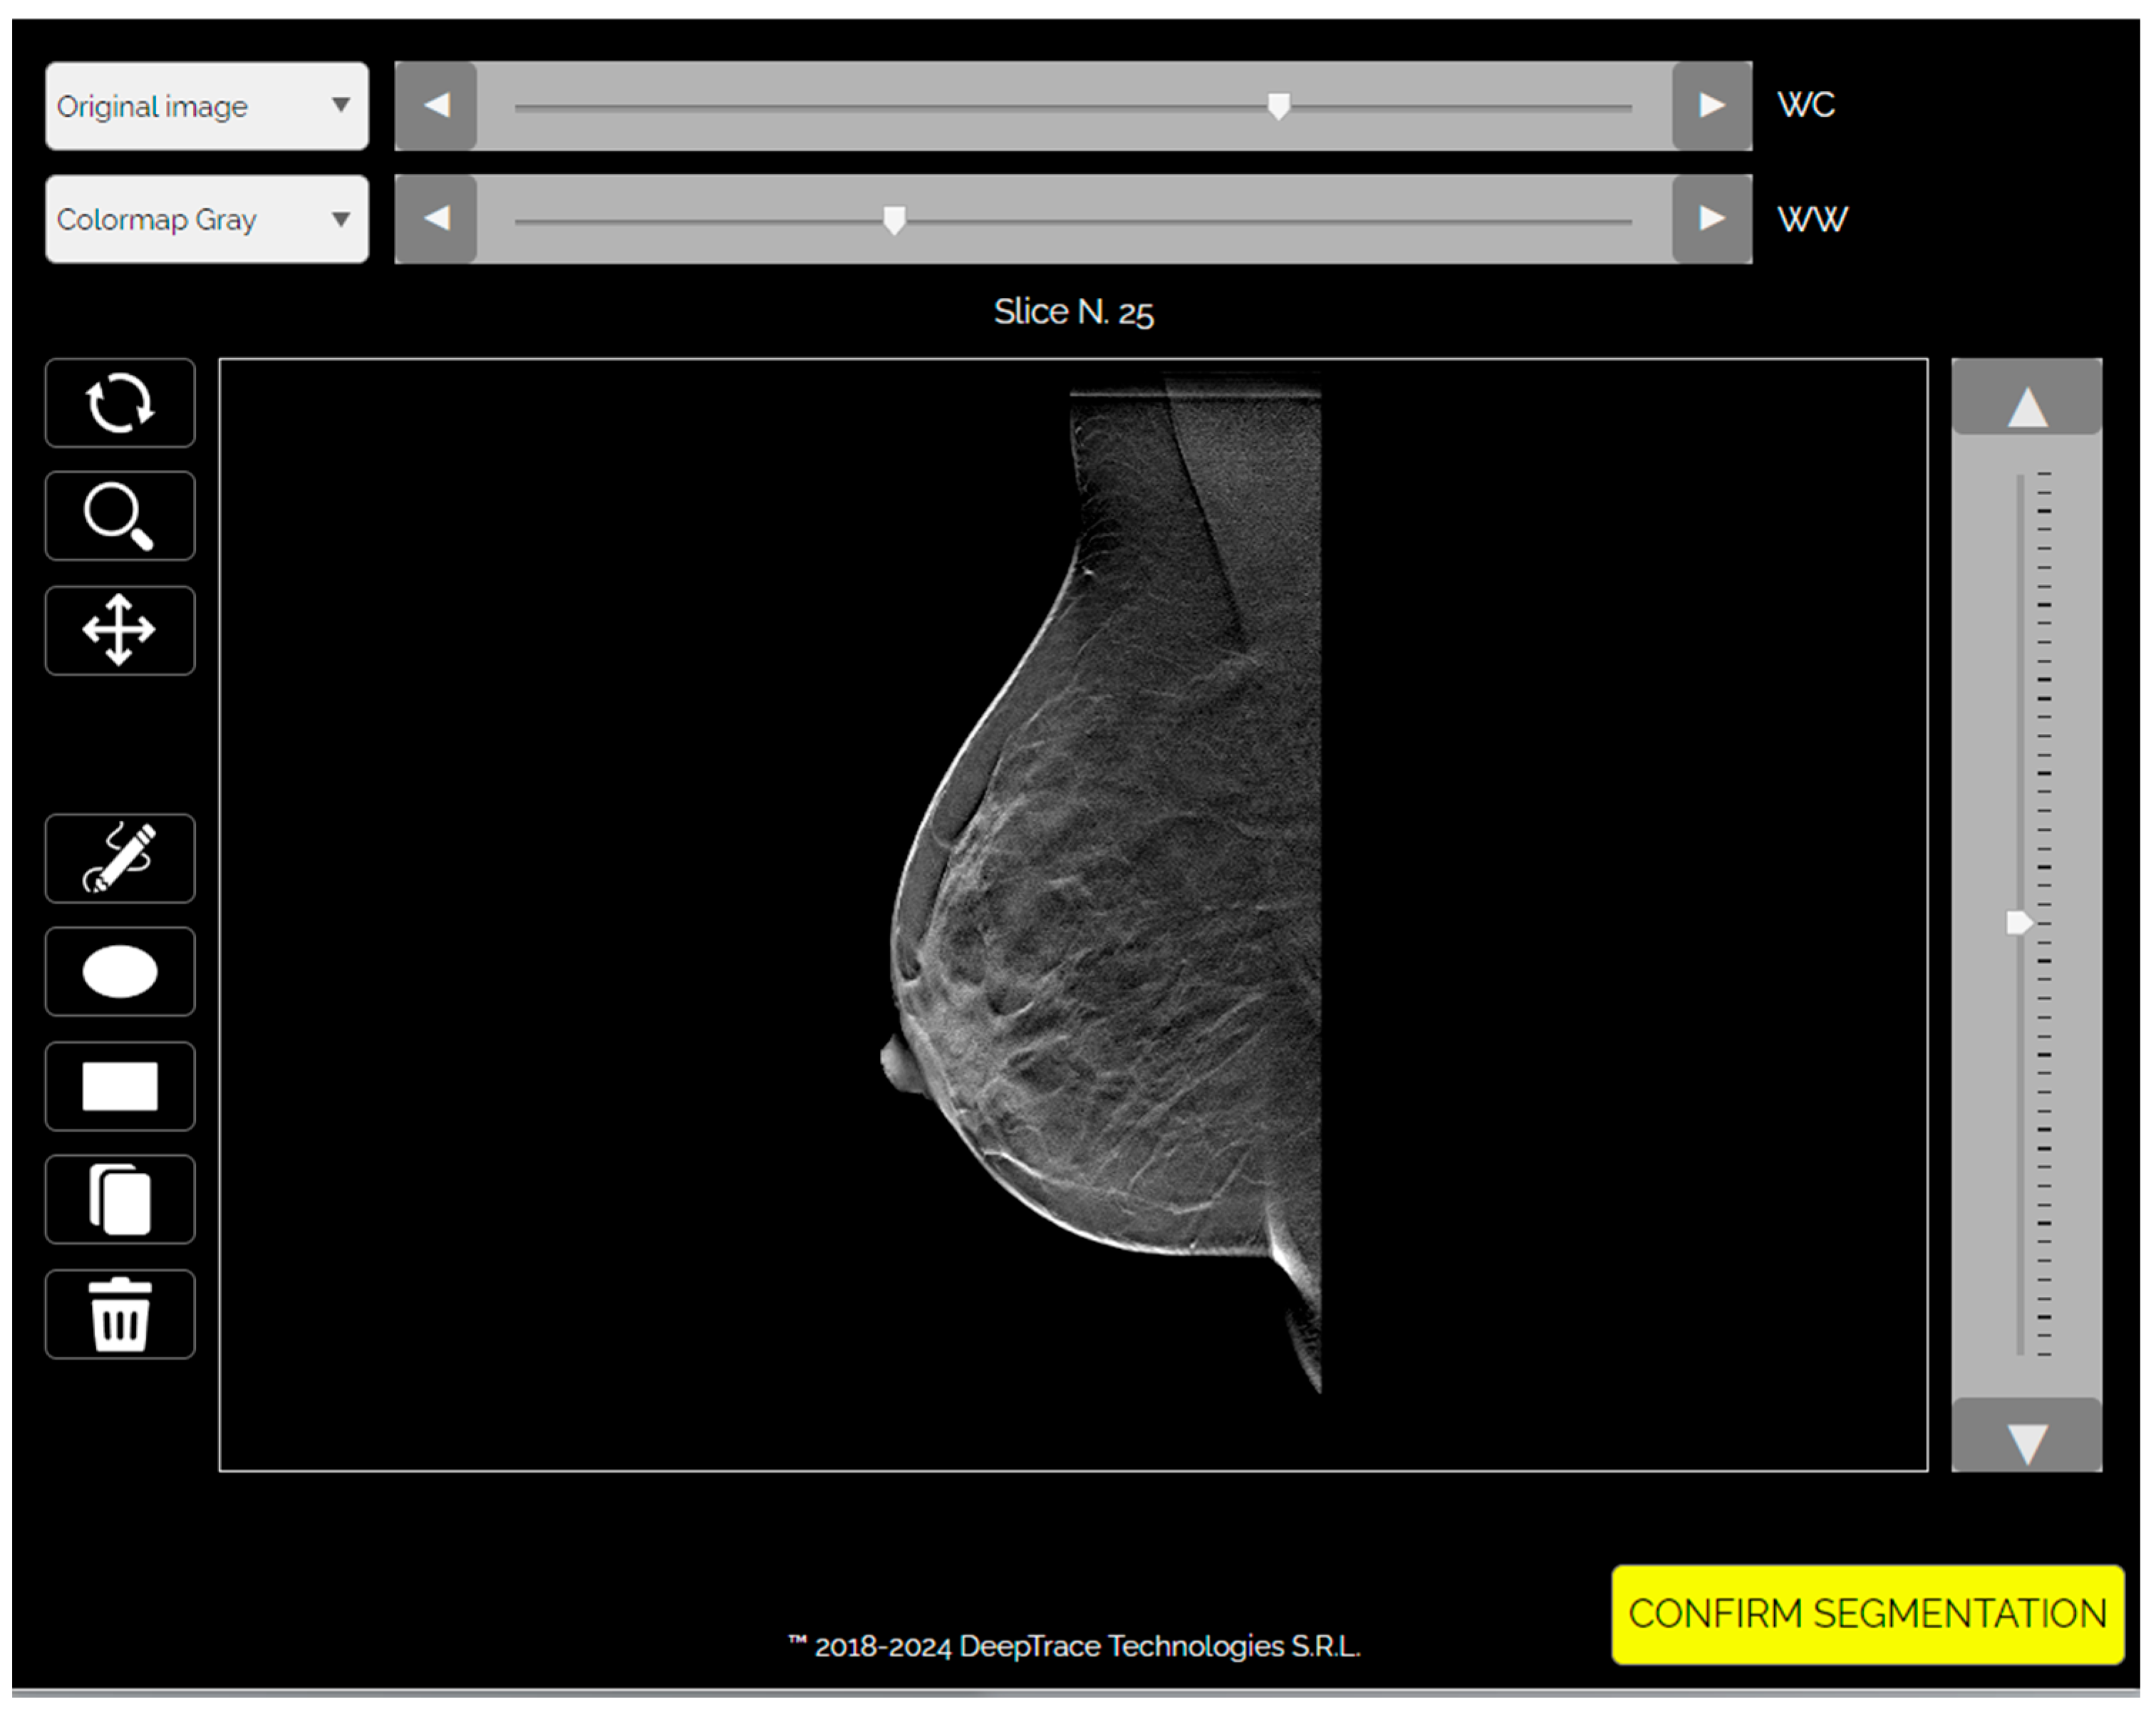

Figure 2. Representative digital breast tomosynthesis (DBT) cases used in the study. The left panel shows a negative case with no radiological evidence of malignancy, classified as BI-RADS 2 and confirmed negative at one-year follow-up. The right panel presents a positive case with a spiculated mass consistent with malignancy, classified as BI-RADS 5 and confirmed as invasive carcinoma on histopathological analysis. Both cases were included in the training dataset and segmented for deep learning model development.

Images were preprocessed through intensity discretization (256 bins) and resampled to a fixed dimension of 224 × 224 × 53 voxels, with the slice count representing the mean number across the dataset (Figure 1 and Figure 2).